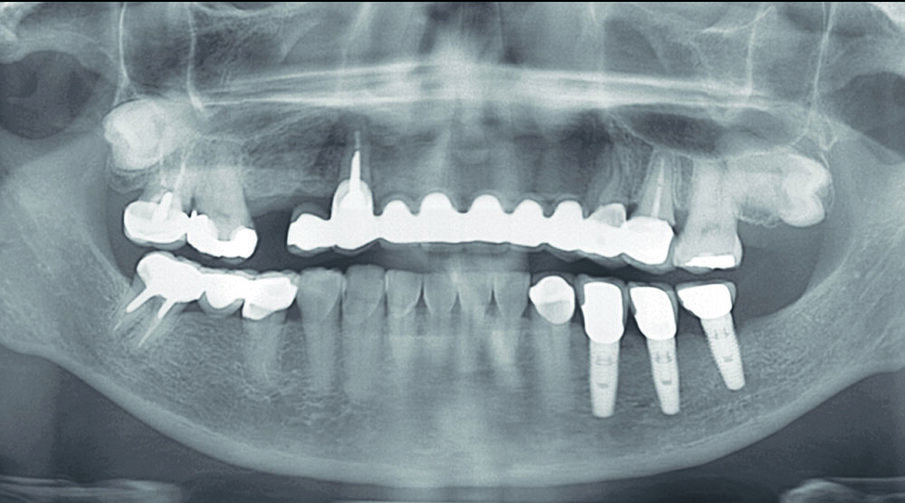

Fig 7. Pre-operative Panoramic XRAY

Fig 22. Post-operative panoramic XRAY

Flapless guided-surgery with immediate loading protocol

The questionable teeth (13, 24 and 25) were extracted under local anaesthesia. The surgical guide was secured in place on the maxillary arch with two anchor pins. (Figs. 21) Flapless surgery was performed using guided tissue punch. Sequential drilling were made according to the manufacturer’s protocol. All implants were placed through the surgical template. All implants were torqued 35 NCm to ensure primary stability. The extraction socket were filled with small particle Xenograft (Bio-Oss, Geistlich) and covered with resorbable collagen plug (Collar plug, Zimmer Biomet). Straight and angle multi-unit abutments were seated and torqued 15 NCm on each implants (Fig. 23)

The existing provisional bridge was utilized for converting to a provisional screw-retained prosthesis. An immediate loading protocol was utilised2. Metal temporary abutments were connected on each implant. Provisional full arch bridge was perforated to match the position of the metal temporary abutments, placed in their correct position and OVD, relined with self-cure acrylic resin. All surfaces were fine-polished. A light-cure denture sealant (Palaseal, Kulzer) was applied on the intaglio surface. The provisional bridge was delivered to the patient’s mouth. (Figs. 23-27) Post-operative panoramic XRAY revealed that implants were placed according to the pre-operative planning (Fig. 22) Suture was removed after surgery 14 days. A final profile protheses3 will be fabricated after implant osseointegration.